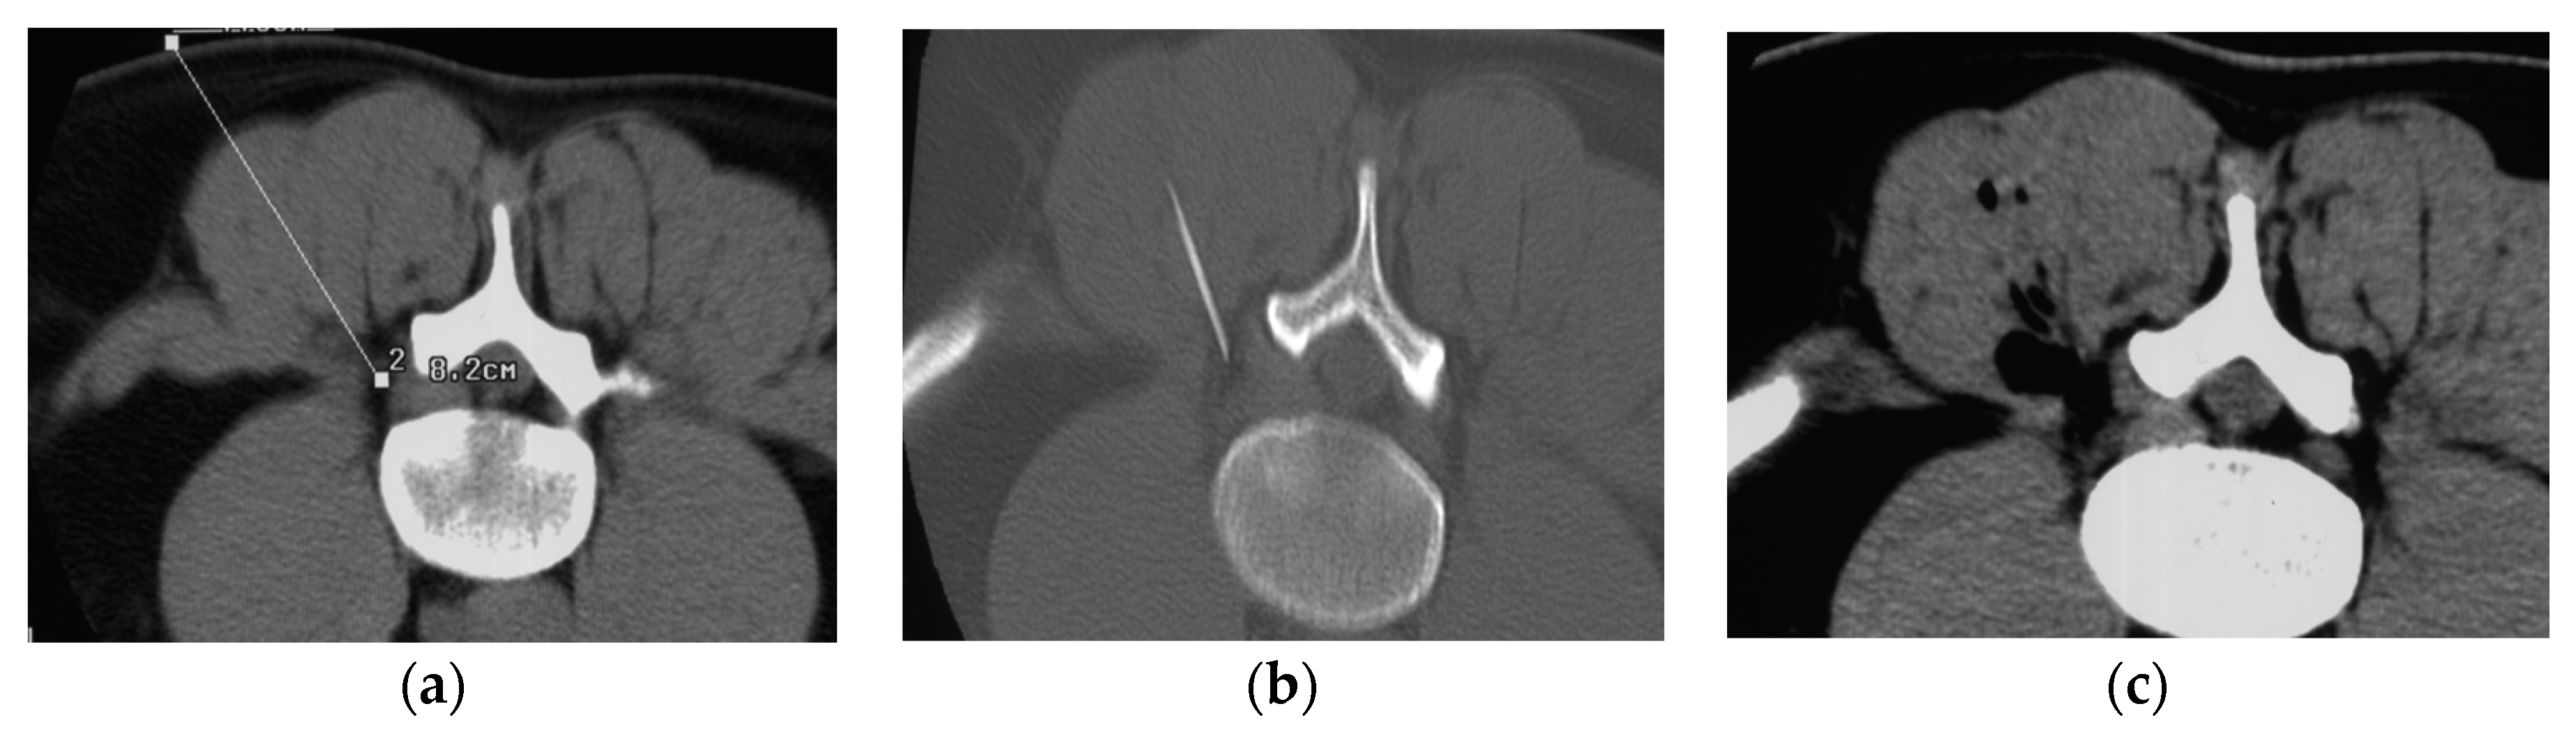

2. Materials and Methods

3. Infiltration Technique